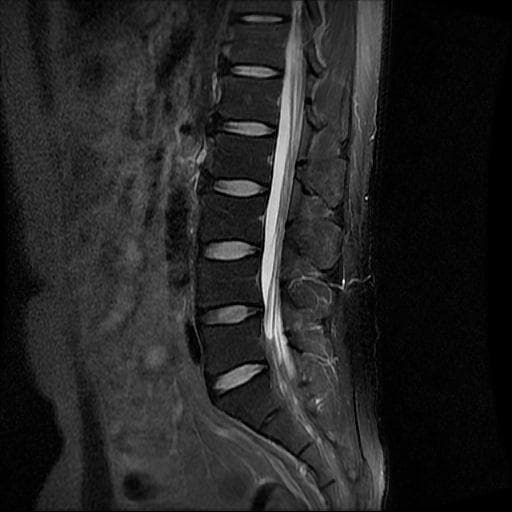

이번에 허리 MRI찍었는데

상태 어떤지 고견 여쭙습니다.

큰 이상이나 문제점은 없어 보이는 것으로 생각되는데요, 허리통증이 지속되는 경우에는 반드시 디스크 질환에 의한것은 아닐 수 있습니다.

현재로썬 디스크 상태는 심하지않는것으로 확인이 됩니다.

MRI 영상 커트로 판독을 할 수는 없습니다.